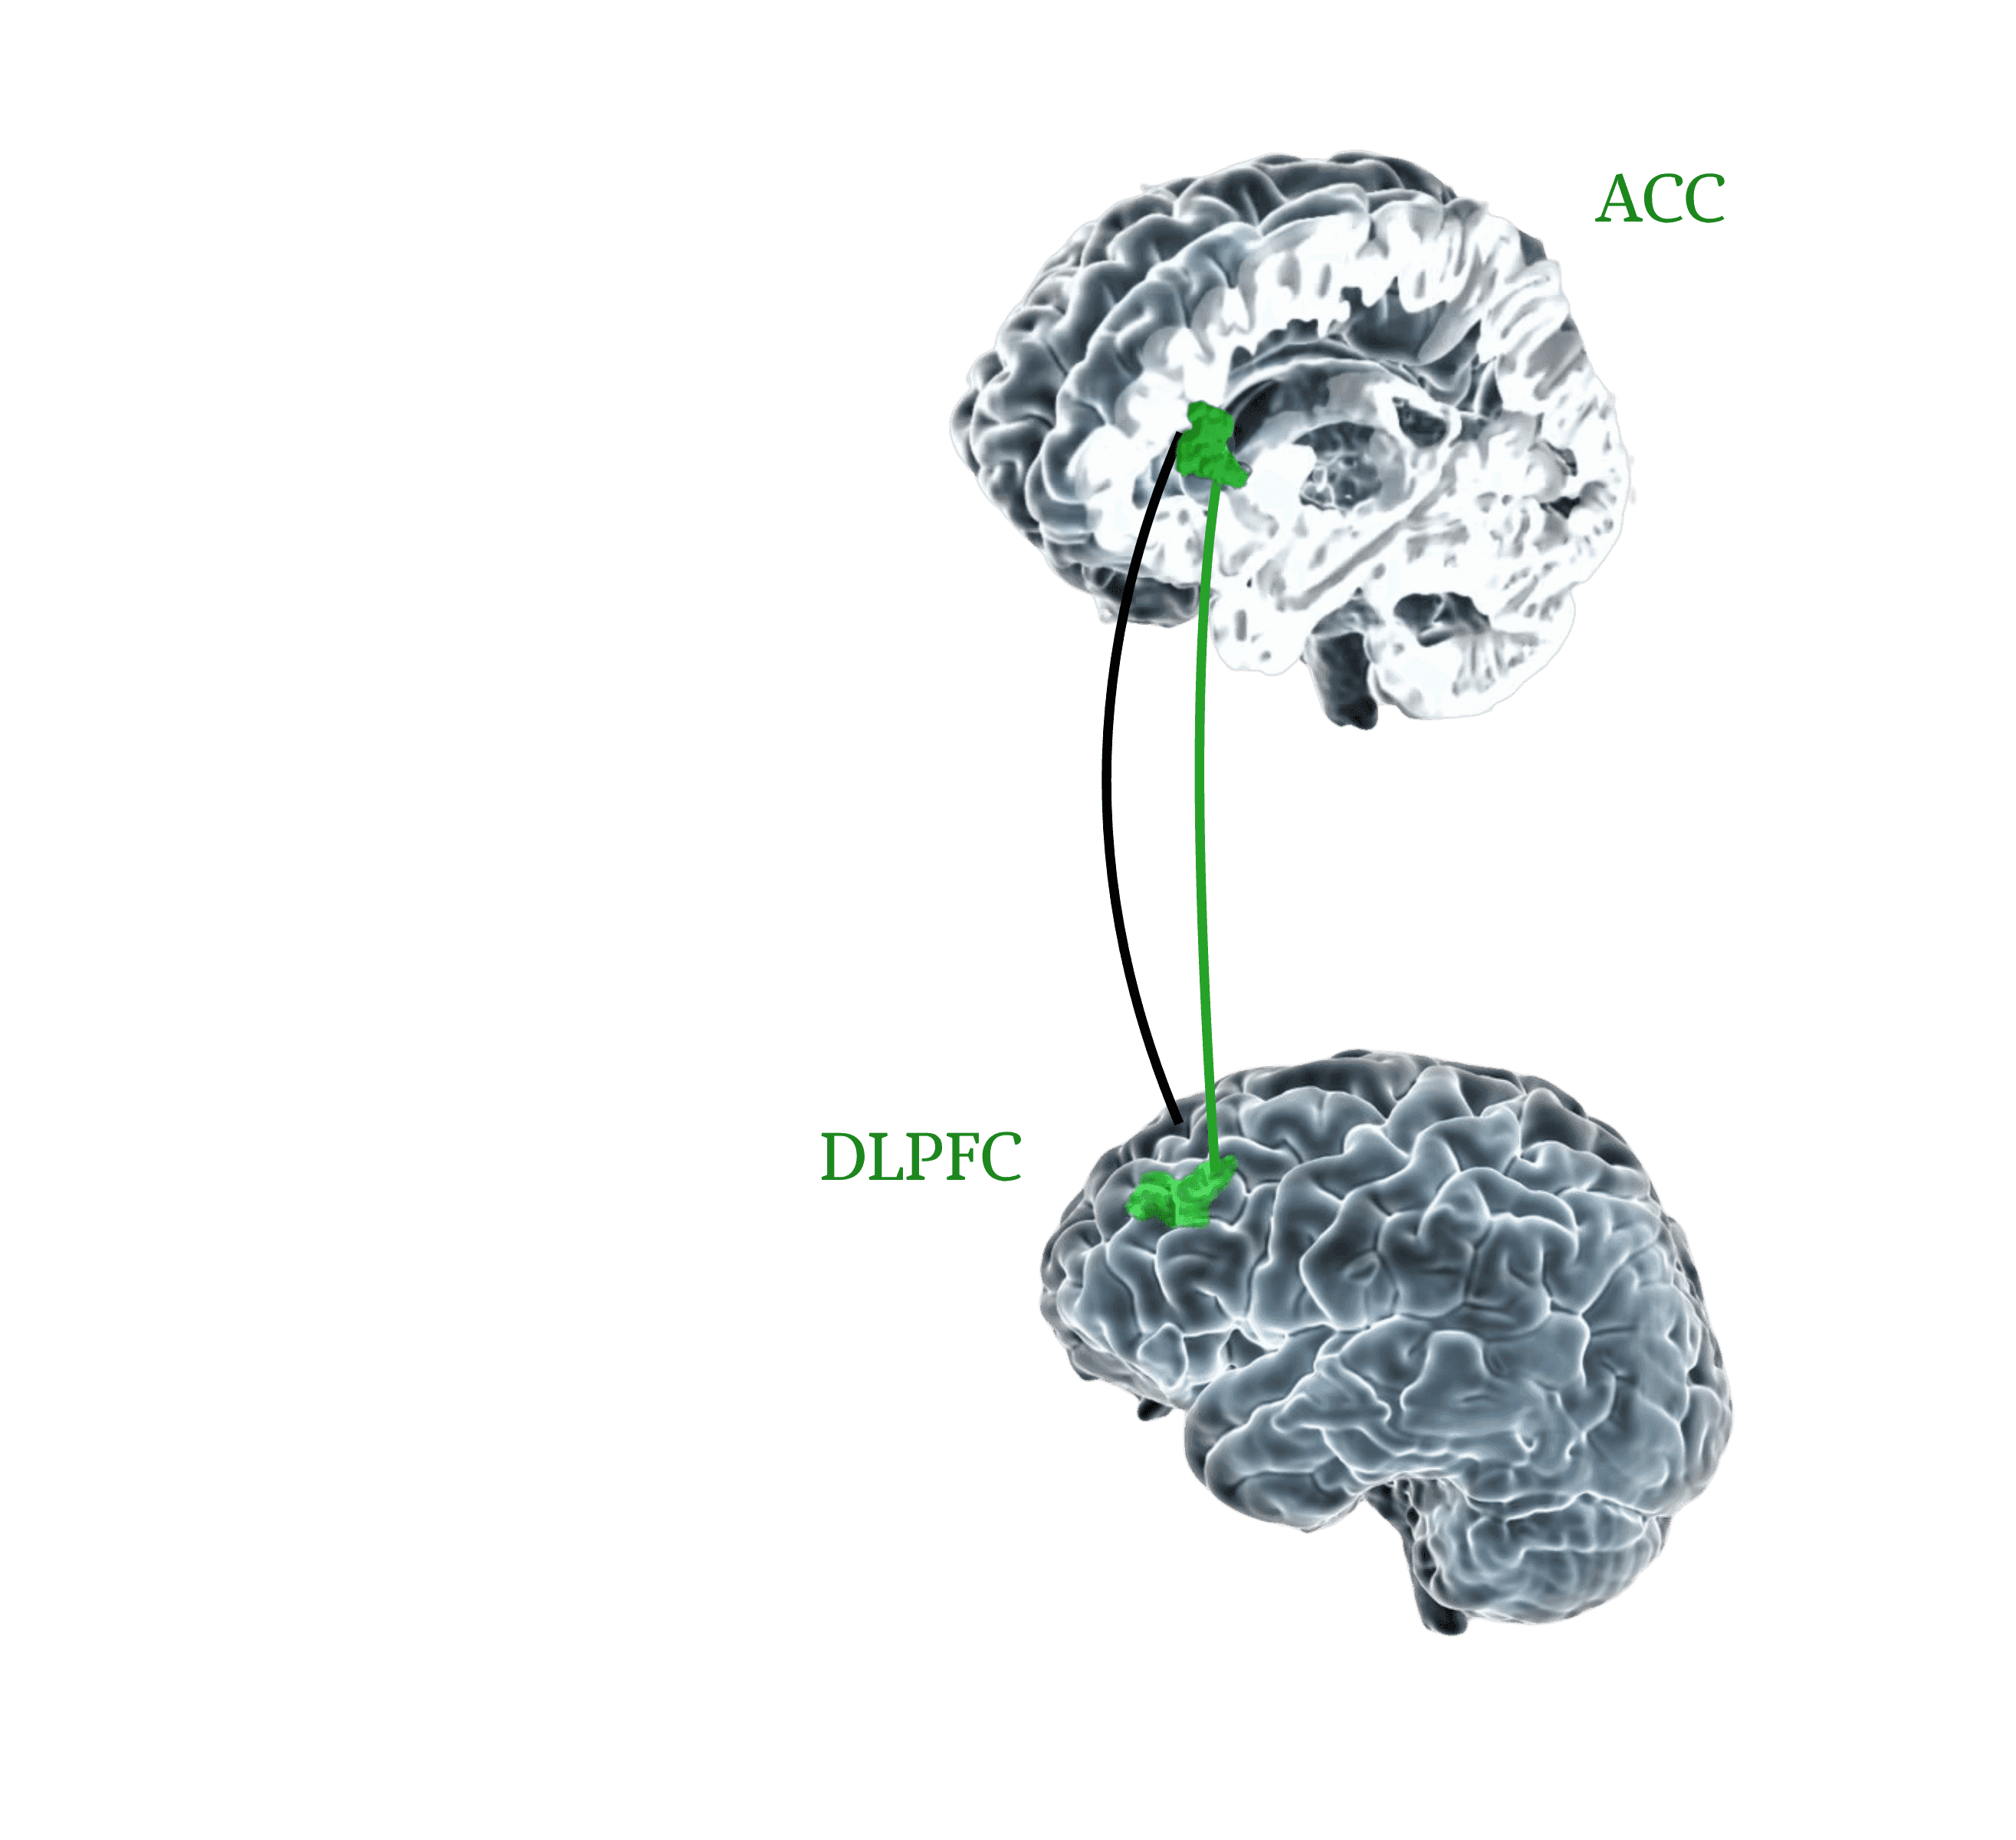

TMS can be used to target specific brain regions, such as the prefrontal cortex, without affecting the entire body.

The two methods also differ in their mechanisms of action: TMS uses magnetic pulses to gradually and precisely modulate activity in targeted areas of the brain, while ECT induces seizures using electrical currents.